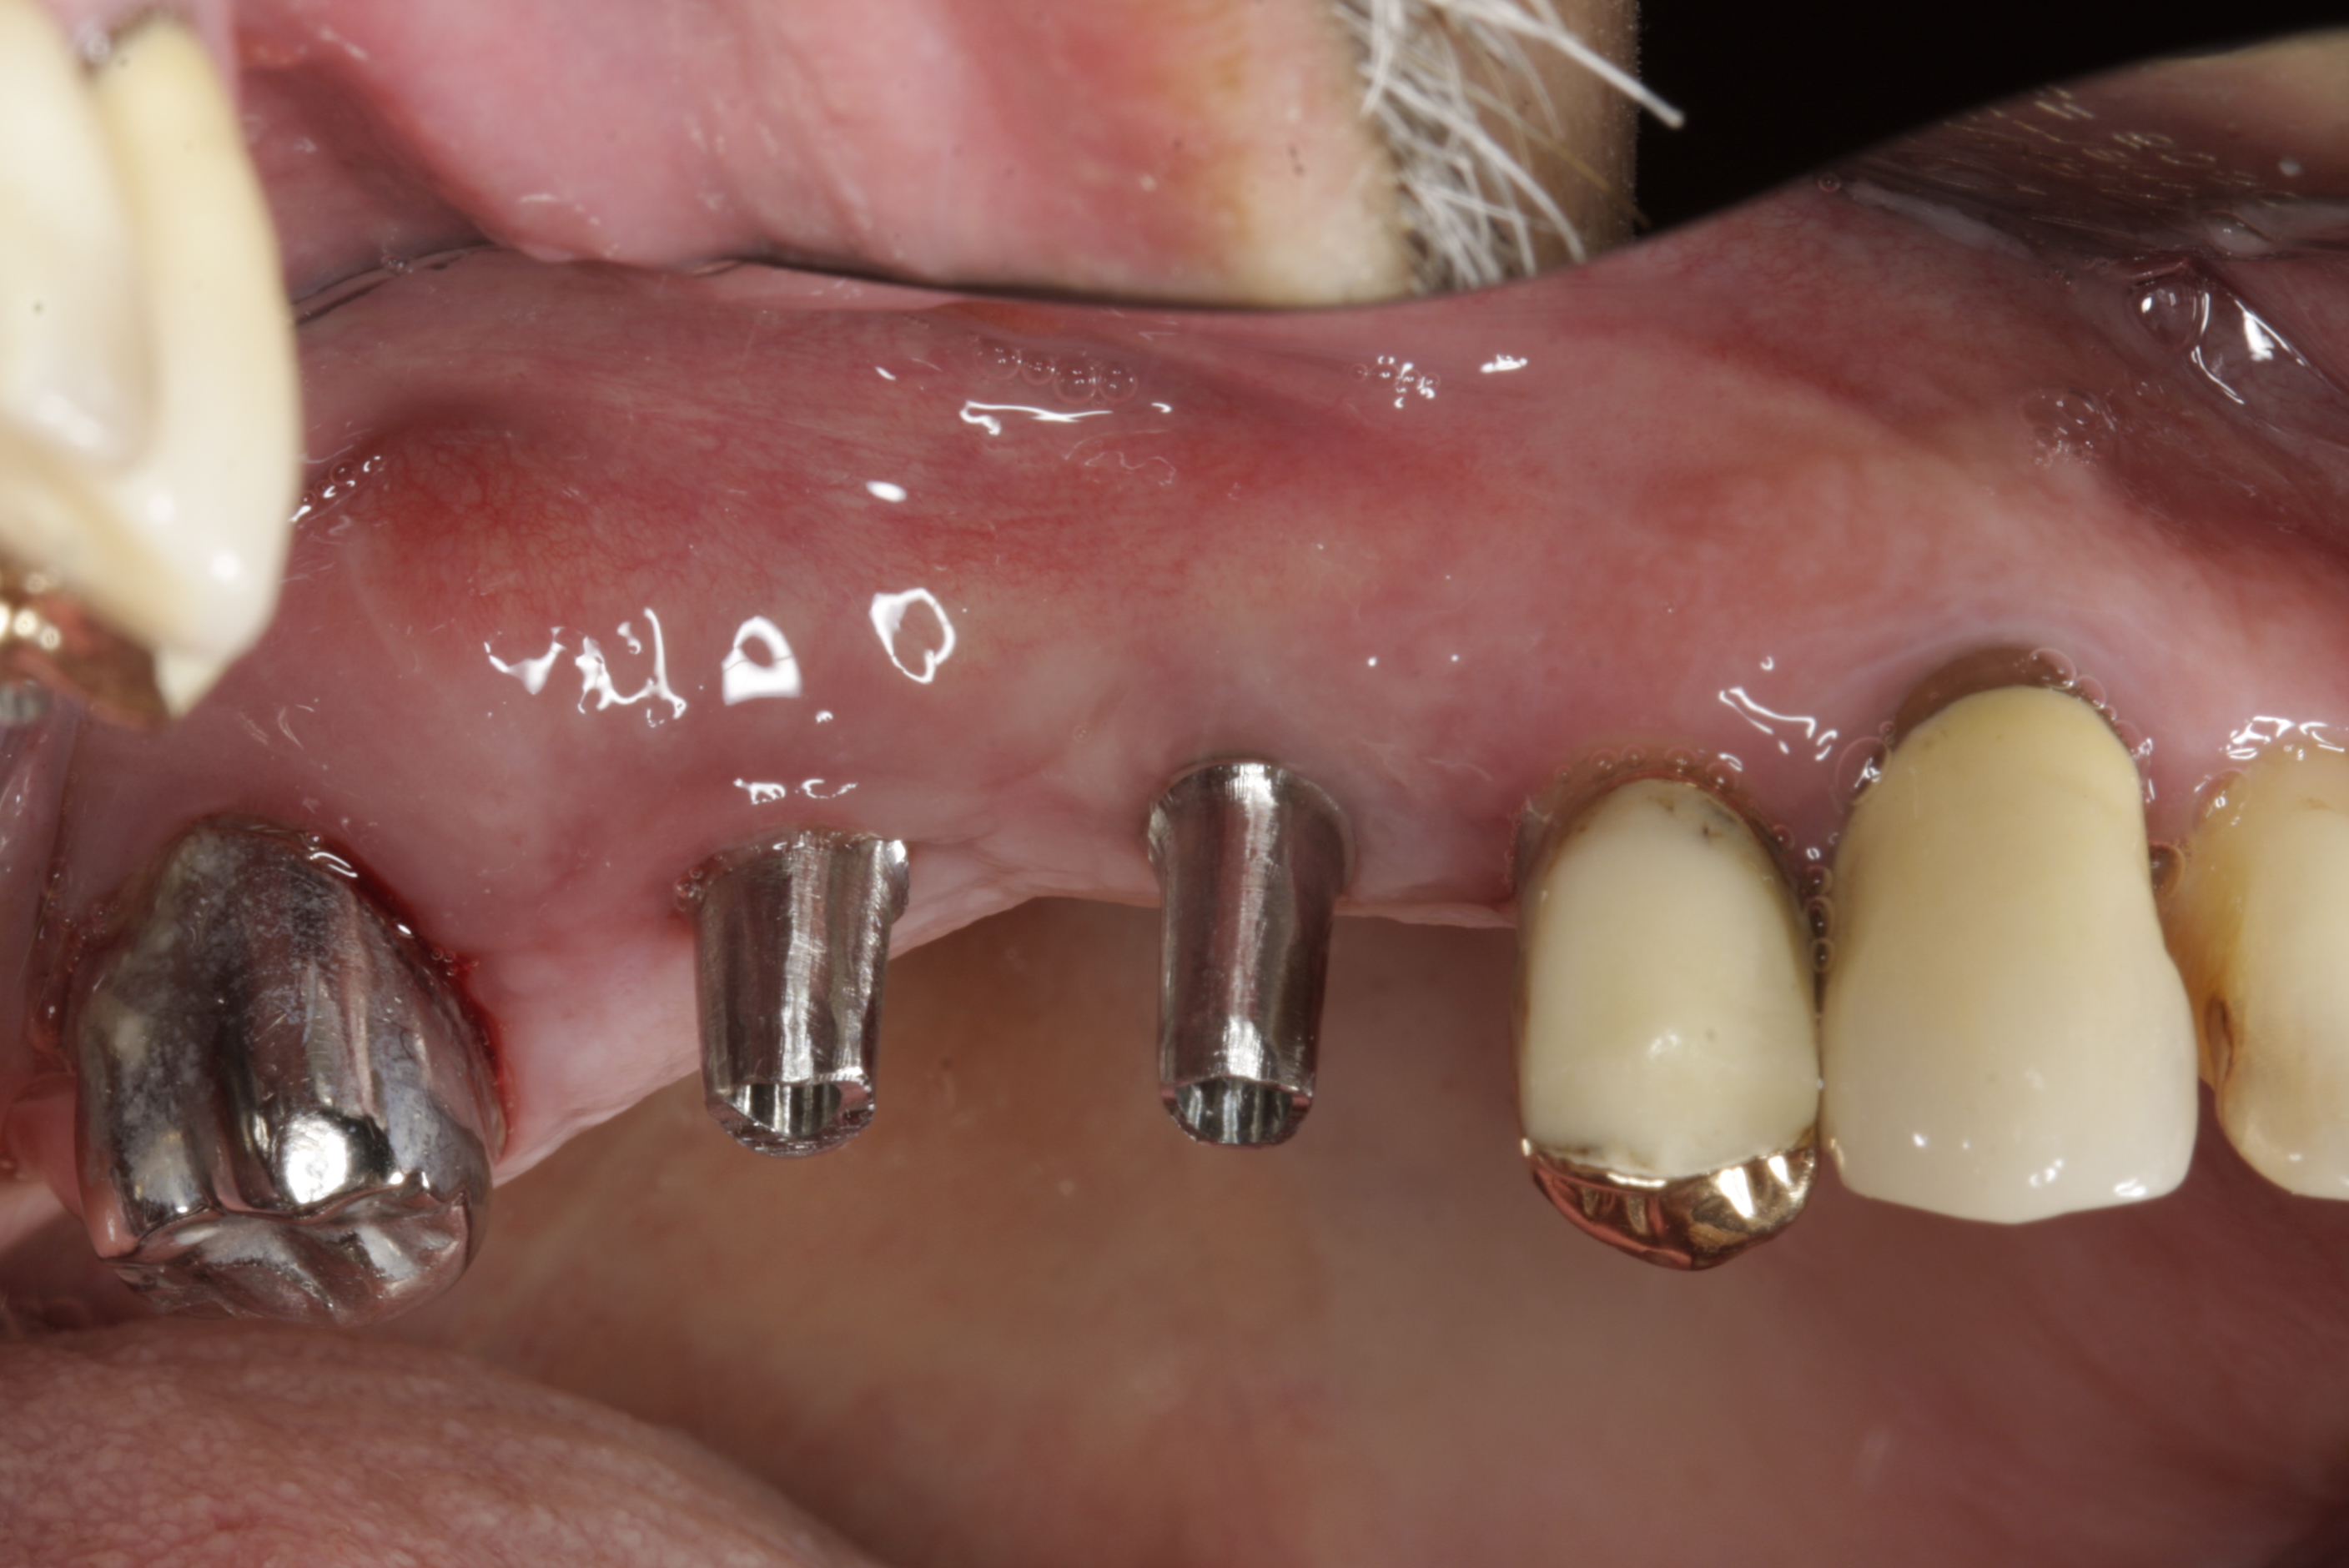

Během let může postupnou ztrátou zubů zůstat v ústech omezený počet zubů, které umožňují držení zubních náhrad.

V důsledku přetížení zbylých zubů např. houpavými pohyb snímacích náhrad dochází k uvolnění těchto zubů a držení můstků a protéz je tak velmi těžké. V těchto případech můžeme pomocí implantátů zvýšit počet pilířů a tím zabránit přetěžování a ztrátě zbylých zubů